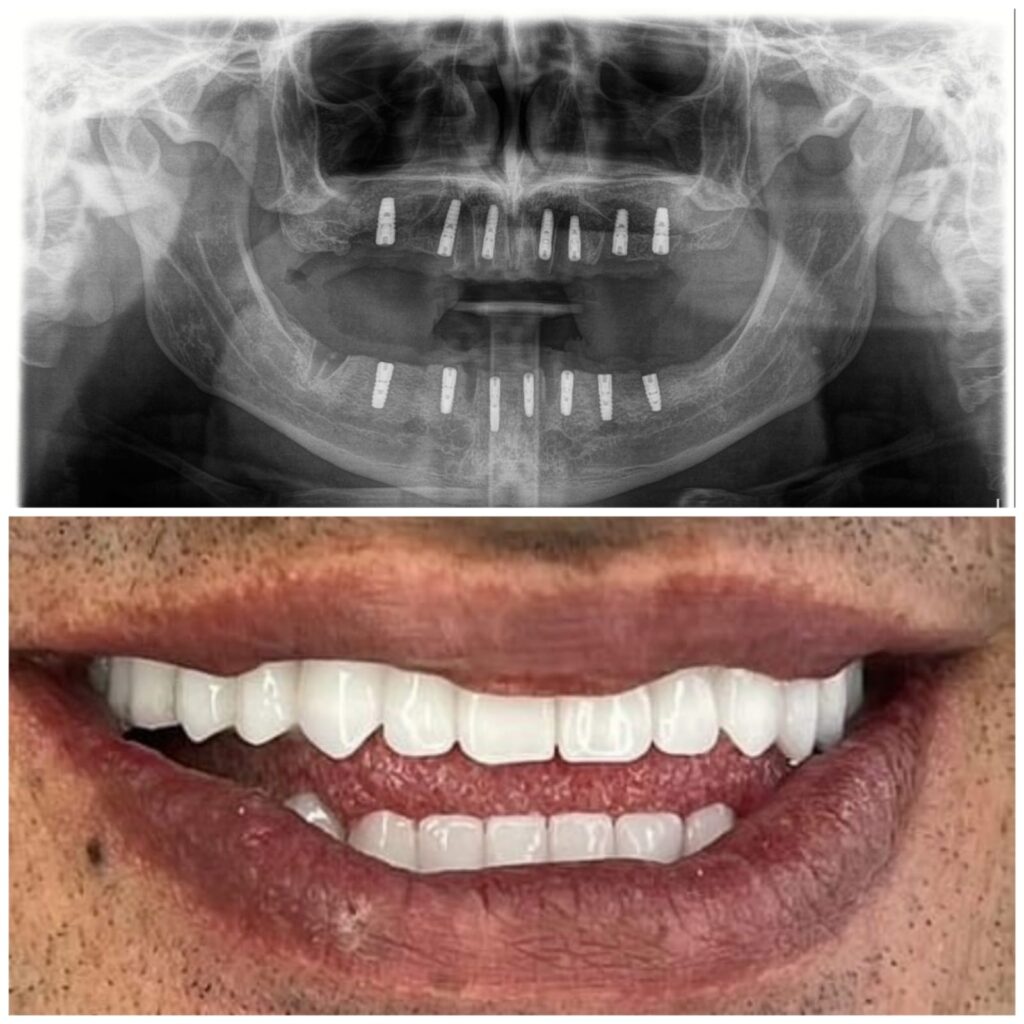

يترأس مراكزنا فريق مختار بعناية من خبراء زراعة الأسنان. وبعد عملية الزرع يتم تركيب التيجان والجسور ، والتي يتم تصميمها بأقصى قدر من الدقة والجمالية لمنحك الابتسامة المثالية.

لقد حققنا نجاحاً في مجالنا ، حيث قمنا بعمل الآلاف من عمليات الزرع للأشخاص في جميع أنحاء العالم بمعدل نجاح بلغ 96٪.

يتم تخطيط وتنفيذ إجراء زراعة الأسنان بعناية لضمان أن ترميم الأسنان يبدو طبيعيًا في الشكل واللون والمكان. نعطي الأولوية لراحة مرضانا بالإضافة إلى الجماليات. وهذا يتطلب مزيجًا مثاليًا من العبقرية الفنية والجراحية. لذلك ، يتم تنفيذ جميع حالات الزرع لدينا من قبل فريق من أطباء الأسنان التجميليين وأخصائي زراعة الأسنان.